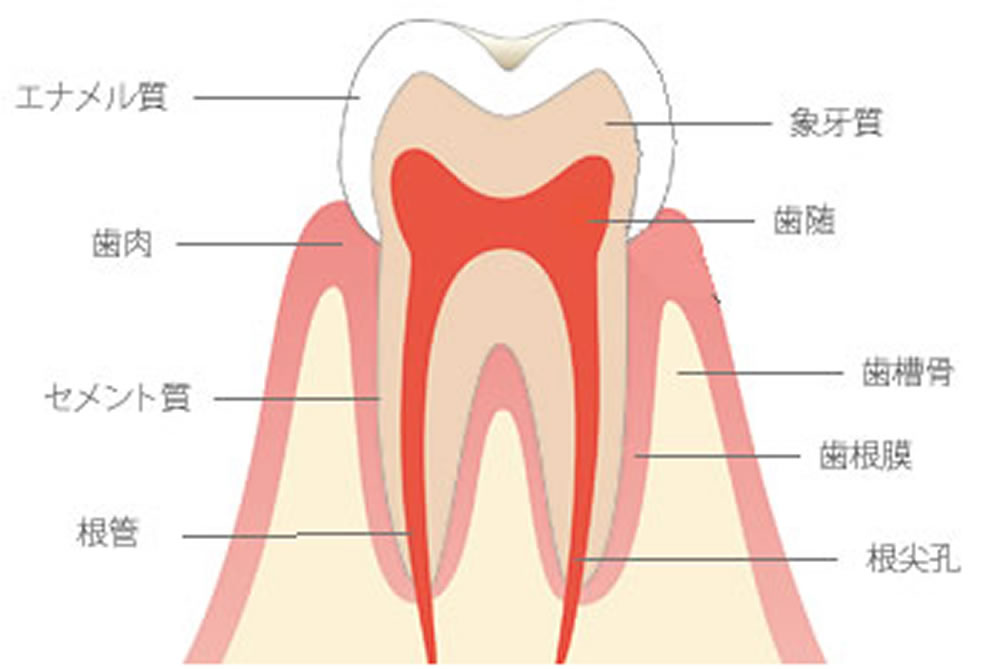

模式図です。

歯の表面はエナメル質が、その内部には象牙質があり、さらにその中に歯髄と呼ばれるものがあります。

歯髄は根管の中を通り、体の中へ抜けていきます。

歯髄は神経と血管で構成されます。